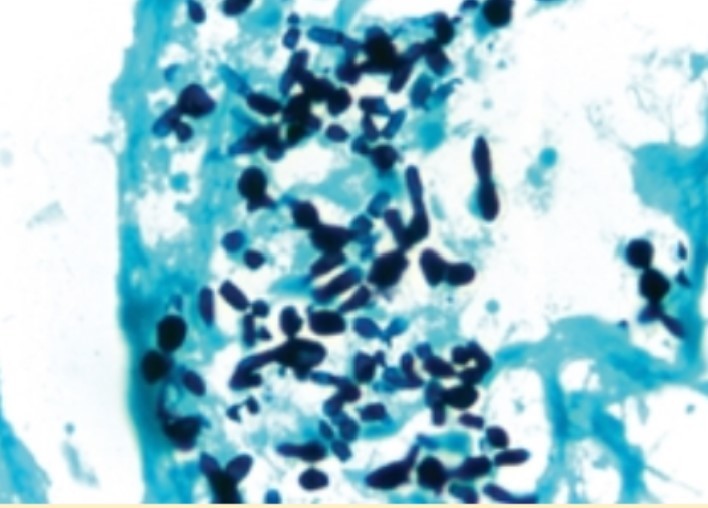

acellular, foamy, eosinophilic, intra-alveolar exudates on H&E

GMS/PAS stains on path = cysts (diff from alveolar proteinosis)

PJP